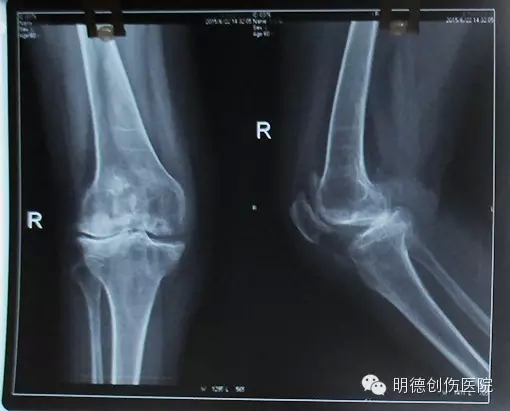

光山县人民医院骨科成功开展全膝关节置换术

青岛海慈医院王相利 你的膝关节炎适合做膝关节置换手术吗